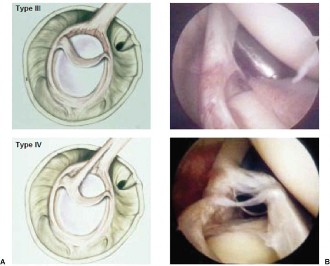

The surgical decision-making process is heavily reliant on the accurate classification of the SLAP lesion. The original classification by Snyder describes four distinct types:

* Type I: Fraying and degeneration of the superior labrum with an intact biceps anchor. Typically treated with arthroscopic debridement.

* Type II: Detachment of the superior labrum and the biceps anchor from the superior glenoid. This is the classic lesion seen in overhead athletes due to the peel-back mechanism. It is further subdivided into anterior, posterior, or combined anterior-posterior detachment.

* Type III: A bucket-handle tear of the superior labrum with an intact biceps anchor. Treated with excision of the bucket-handle fragment.

* Type IV: A bucket-handle tear of the superior labrum that extends into the biceps tendon. Treatment depends on the extent of biceps involvement (repair vs. tenodesis).

Subsequent authors have expanded this classification (Types V through X) to include extensions into the anterior labrum (Bankart), the posterior labrum, or the middle glenohumeral ligament. Based on the MRA and clinical exam, our patient presents with a classic Type II SLAP lesion with posterior extension.